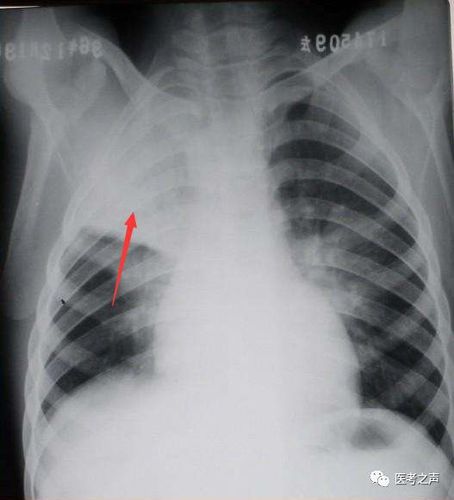

病毒性肺炎丨ct表现,诊断要点_小叶

急求教以下病例怎样区分大叶性小叶性肺炎在线等谢谢

② 小叶性肺炎